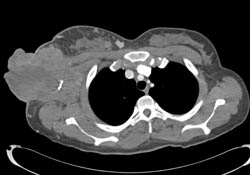

Right Upper Lobe Nodule and Infiltrate Left Lower Lobe